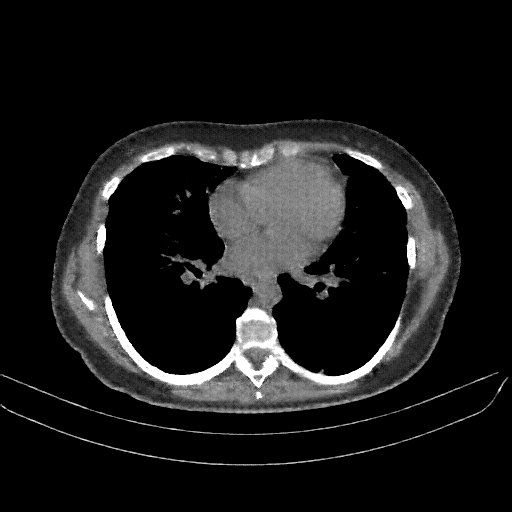

Reconstructed NATIVE CT scan (cycle consistency)

Full window (WL 1023.5, WW 4095 β†’ Low βˆ’1024, High +3071)

Lung window (WL -600, WW 1500 β†’ Low βˆ’1350, High +150)

Mediastinum window (WL 40, WW 400 β†’ Low βˆ’160, High +240)